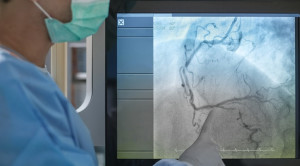

Percutaneous coronary intervention atau intervensi koroner perkutan pada sindrom koroner akut dapat dilakukan dengan pendekatan radial atau femoral. Masing-masing pendekatan ini mempunyai...(Baca Selengkapnya)